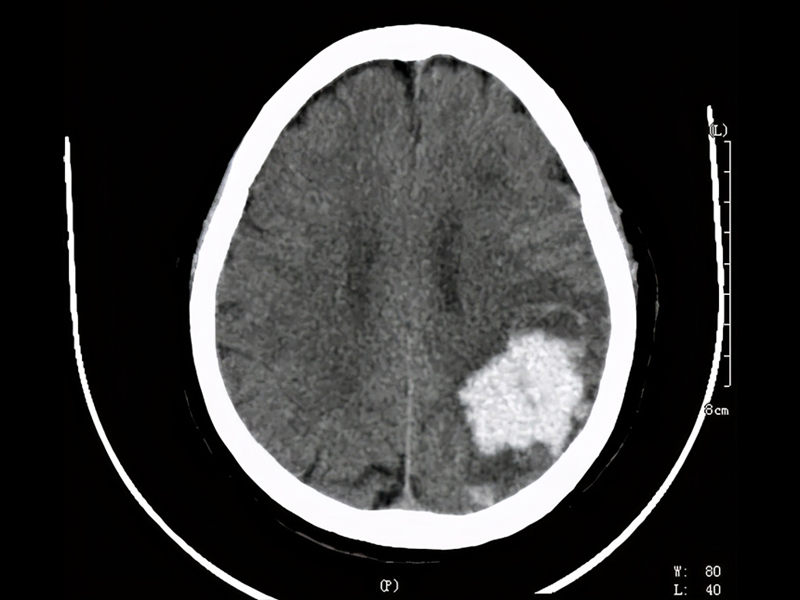

腦幹出血是神經系統的重症,疾病死亡率高。腦幹出血量在 15ml 以下,死亡率約 17.1% 左右;出血量高於 15ml 以上,死亡率 81.8% 左右;若超過20ml死亡率更高。

高血壓動脈硬化是腦幹出血的主要病因,腦幹出血是因高血壓導致基底動脈中央之破裂引起。在數秒到數分鐘內患者就會昏迷、四肢癱、針尖般瞳孔,數小時內會死亡。

據報道,這名程序員吳先生從事技術工作,月薪高達 3 萬元人民幣,但每天的工作時間從早上 7 點持續到凌晨 1 至 2 點,長期處於極度疲勞狀態。今年年初,他因腦幹出血 5 毫升陷入昏迷,昏迷長達 15 天,在 ICU 搶救 28 天後才逐漸恢復意識。隨後,他又轉入康復醫院進行 70 多天的治療,目前已恢復約 70% 的身體功能,但仍無法完全康復。